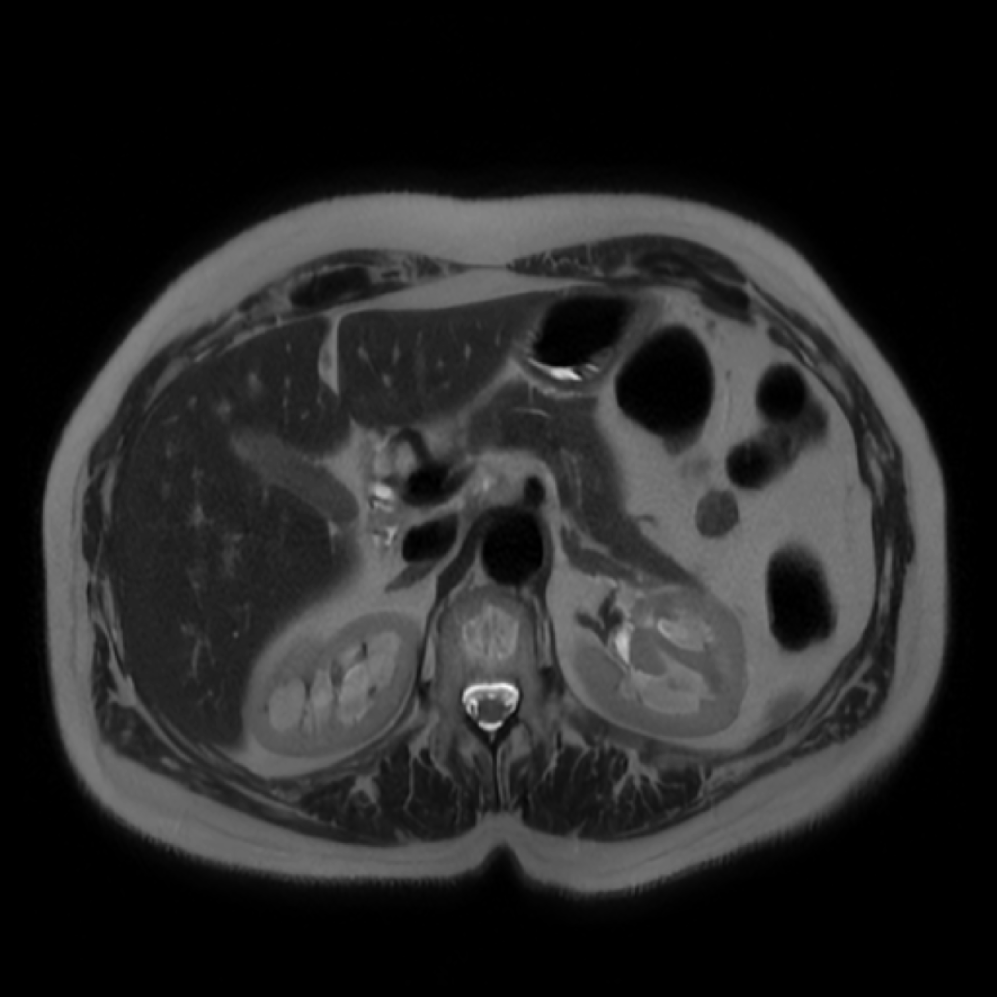

Each patient was categorized into one of these three ground truth classes: no risk/control, IPMN low-risk, or IPMN high-risk. To evaluate variability in image acquisition, we applied uniform manifold approximation and projection (UMAP) to image quality indicators, revealing distinct clustering patterns by imaging center and slice thickness. This heterogeneity reflects real-world clinical variability, enhancing the dataset’s generalizability while presenting technical challenges for model development. Fig. 6 shows examples of low-grade, high-grade, and cancer developing IPMNs from the Cyst-X dataset.

Accurate pancreas segmentation is a critical prerequisite for precise cyst analysis and classification. Recently, we developed PanSegNet [zhang2025large], a novel segmentation architecture incorporating linear self-attention layers [zhang2022dynamic] within the nnUNet framework [isensee2021nnu] to enhance global information modeling capabilities while maintaining computational efficiency (Fig. 1). PanSegNet demonstrated exceptional segmentation performance across both T1W and T2W modalities, achieving mean dice scores of 86.817.30% and 89.626.38%, respectively (Table 1, Fig. 2b-c). This performance significantly exceeded that of Swin-UNETR [hatamizadeh2021swin], one of the most used state-of-the-art transformer-based medical segmentation models, which achieved dice scores of 79.091.40% and 76.290.66% for T1W and T2W, respectively (). In this study, we integrated PanSegNet into our Cyst-X engine along with a classifier for risk prediction. In Section 2.2, we show that the choice of segmentation model affects the classification results. The performance advantage of PanSegNet was consistent across all seven medical centers, demonstrating robust generalization despite variations in imaging protocols and equipment (Table 1). This cross-institutional reliability is particularly important for clinical applications, where model performance must remain consistent regardless of imaging site or acquisition parameters.